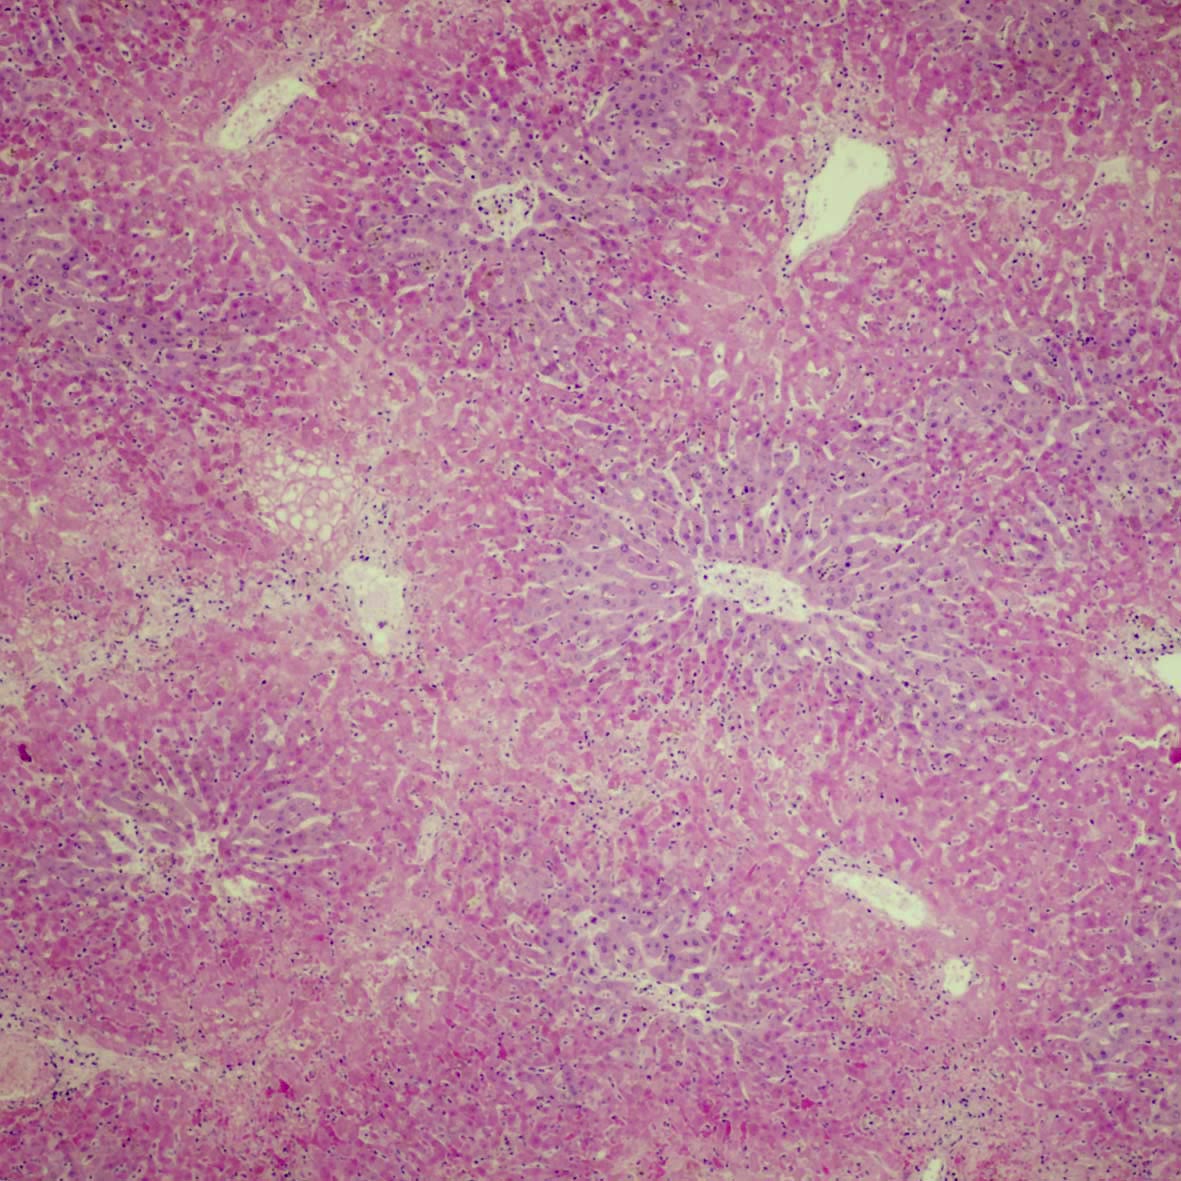

In this view, several complete lobules can be seen and there is marked acute hepatocellular necrosis (pinker colour) with only the hepatocytes (bluer colour) close to the central vein (whitish 'hole') being spared. This picture is typical of RHD. RHDV2 was confirmed by PCR testing in this case.